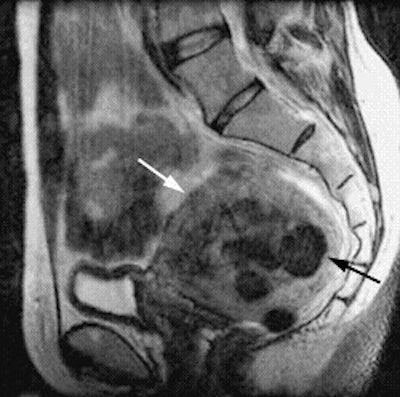

![]() |

| The same patient six months after the UFE procedure. This sagittal, T1-weighted midline MR image shows a 50% decrease in the size of the uterus (white arrow). The fibroids have low signal (black arrow), consistent with devascularization. The patient reported complete relief of symptoms. Image courtesy of Dr. Steven Janney Smith. |